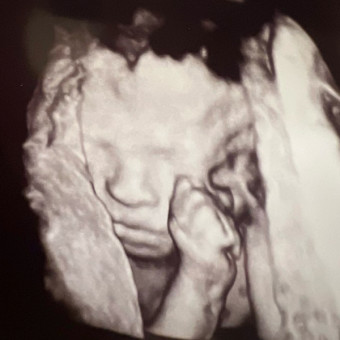

Elisa's Baby Registry

Elisa Glubok Gonzalez & Dylan Daniels

March 13, 2026

We are so grateful for the community we have to welcome our baby! Gifts are NOT expected - we are just excited to celebrate with you! We will also gladly accept any gently used, previously loved items. Thank you for already showering this baby with so much love!